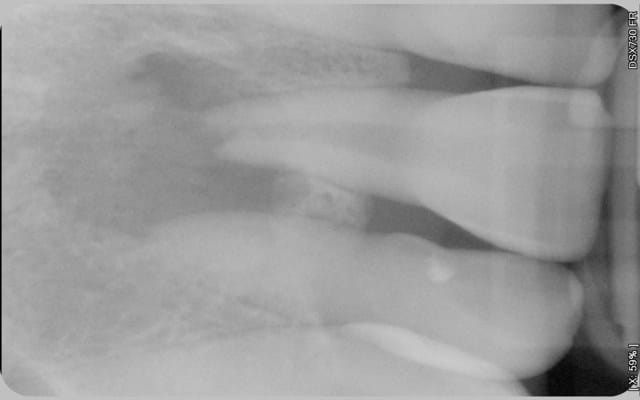

Suite à un choc, un patient présente un kyste important et une résorption externe de la 11. L'apex est complétement ouvert. La table osseuse vestibulaire a disparu.

Voici les photos.

Comme vous pouvez le voir la lésion est très importante. Pensez-vous que cette dent ai une chance? Mon maître de stage lui laissait 40% de chance, je n'ai pas de recul mais ça me semble beaucoup. J'ai preferé dire au patient que ça serrait délicat car il n'imaginait même pas la possibilité d'enlever la dent.

J'ai déjà vu des lésions plus grosses que ça, fistulisées, bien cicatriser après l'endo.

Ton traitement est perfectible en longueur et en densité.

Envoie au service endo de ta fac pour désobturer et refaire le traitement avec pose d'un bouchon de MTA, si tu n'as pas la possibilité de le faire toi-même. La cicatrisation de cette lésion est tout à fait possible. Surtout ne pas extraire en première intention. Pour évaluer l'épaisseur de la corticale externe tu peux demander un cone beam.

Retraitement - en fonction du diamètre apical cone moulé ou bouchon de MTA.

Surveillance

Si non cicatrisation : chir endo avec obturation a retro.